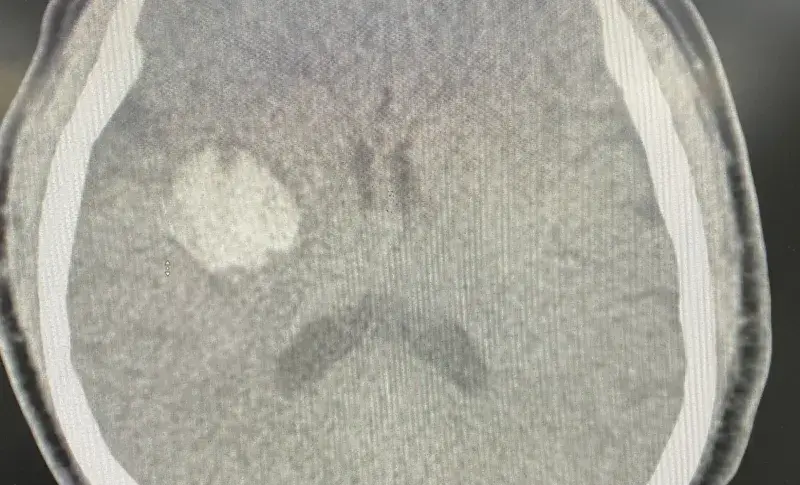

Ngay khi vào Trung tâm Đột quỵ, người bệnh được thăm khám và chẩn đoán ban đầu là có tình trạng rung giật nhãn cầu, nhìn đôi, tê yếu 1/2 người phải, cơ lực 3-4/5. Người bệnh được chỉ định chụp cộng hưởng từ sọ não, kết quả cho thấy có hình ảnh nhồi máu não hành não phải, nguyên nhân gây ra tình trạng trên là do tắc một nhánh mạch nhỏ của hệ tuần hoàn não. Người bệnh được chẩn đoán đột quỵ nhồi máu não cấp hành não phải.